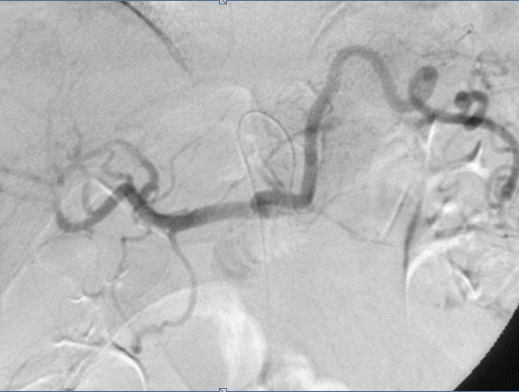

L'arteriographie

: Technique radiologique de choix pour explorer

l'artere splenique , les branches , la

vascularisation des lesions splenique et les extravasions

parenchymateuses spleniques